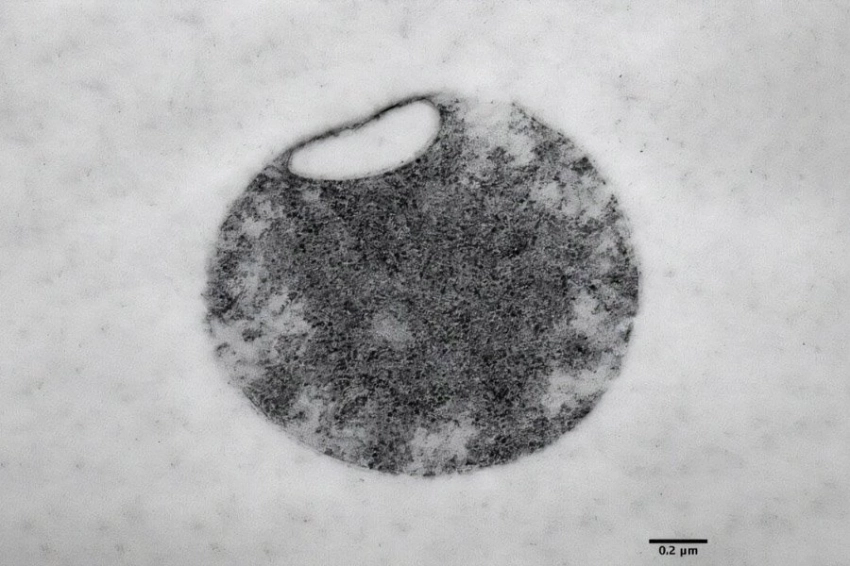

Мини-сердца созданы из человеческих плюрипотентных стволовых клеток (hPSC). Это клетки с особыми свойствами: они могут неограниченно размножаться в культуре и образовывать любой тип клеток. С помощью биологических или химических сигналов, встроенных в гидрогелевую матрицу, hPSC можно контролировать таким образом, что трехмерные клеточные агрегаты развиваются в сердечные органоиды за 10–14 дней. Это не скопления клеток сердечной мышцы, а сложные структуры, состоящие по меньшей мере из семи различных, четко структурированных типов клеток и тканей.

Как и в естественном эмбриональном развитии , искусственное мини-сердце состоит из трех чашеобразных слоев и включает зачаток сердца, предшественников печени и легких, а также кровеносных сосудов.